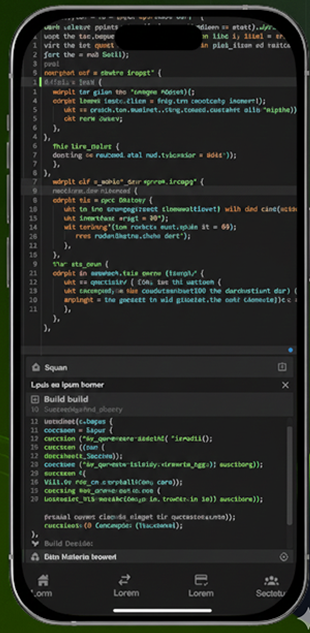

With our EHR, seamlessly manage clinical operations, administrative workflows, and financial services efficiently in one integrated platform.

Request Demo Request Demo

Manage doctors, nurses, pharmacists, and laboratory services efficiently through a centralized clinical system.

Securely accept and manage patient payments with seamless billing and transaction tracking.

Manage financial operations, administrative activities, and system configurations.